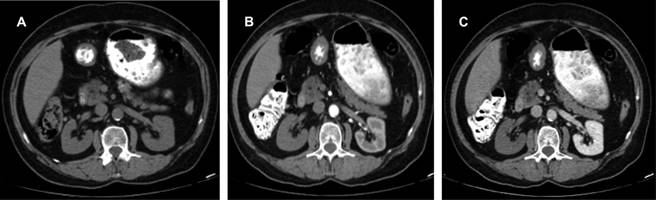

En fase arterial, la angiotomografía evidencia amputación de arteria renal derecha desde su origen con la consecuente ausencia de fase nefrográfica (Figuras 1 y 2).

Figura 1: Estudio angiotomográfico. A) Corte axial en fase simple sin evidencia de alteraciones. B) Corte axial en fase corticomedular que evidencia amputación de arteria renal derecha desde su origen y sin realce de la corteza tras la administración de contraste intravenoso. C) Corte axial en fase nefrográfica que visualiza persistencia de la amputación de arteria renal derecha, sin realce del parénquima renal.